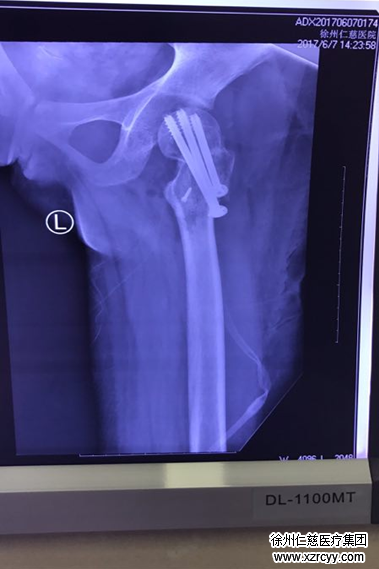

于是,在家人的陪同下,惠惠去醫(yī)院進(jìn)行了復(fù)查。很快,CT報(bào)告出爐??吹狡永镲@示的影像,惠惠和家人頓時(shí)傻了眼:植入惠惠腿里的鋼釘竟然打偏了,也正是這根錯(cuò)位的鋼釘,讓她每天都在承受著鉆心的疼痛!更為嚴(yán)重的是,由于耽擱時(shí)間較長(zhǎng),惠惠的左股骨頸也已隨之移位,左下肢已經(jīng)發(fā)生了短縮畸形,如果不及時(shí)糾正的話,將造成繼發(fā)性損傷,導(dǎo)致股骨頭壞死。到那個(gè)時(shí)候,這個(gè)年輕女孩則必須要面臨股關(guān)節(jié)置換。然而目前市面上最好的人工股關(guān)節(jié)的使用期限也僅僅只有40年,并且價(jià)格比較昂貴,這就意味著,如果二次復(fù)位手術(shù)失敗的話,惠惠將至少面臨兩次股關(guān)節(jié)置換,這對(duì)其本人和家人來(lái)說(shuō),無(wú)論是在經(jīng)濟(jì)上還是身體和精神上都要承擔(dān)難以想象的代價(jià)。

6月7日,惠惠再次躺在了手術(shù)臺(tái)上。經(jīng)過(guò)反復(fù)消毒后,李主任為惠惠進(jìn)行了手術(shù)。術(shù)中,他將惠惠左股骨頸內(nèi)移位松動(dòng)的內(nèi)固定裝置取出,然后再將左股骨相隆處部分松質(zhì)骨取出,置入股骨頸骨折端,通過(guò)牽引、內(nèi)收、內(nèi)旋等一些列復(fù)雜的處理后,將股骨頸骨折處進(jìn)行復(fù)位,經(jīng)過(guò)6、7個(gè)小時(shí)的緊張手術(shù),惠惠的股骨頸骨折端被成功修復(fù)。

“這個(gè)修復(fù)手術(shù)可以用‘完美’來(lái)形容!”聽(tīng)到醫(yī)生傳來(lái)的喜報(bào),在手術(shù)室外焦急等待的惠惠父母禁不住喜極而泣。